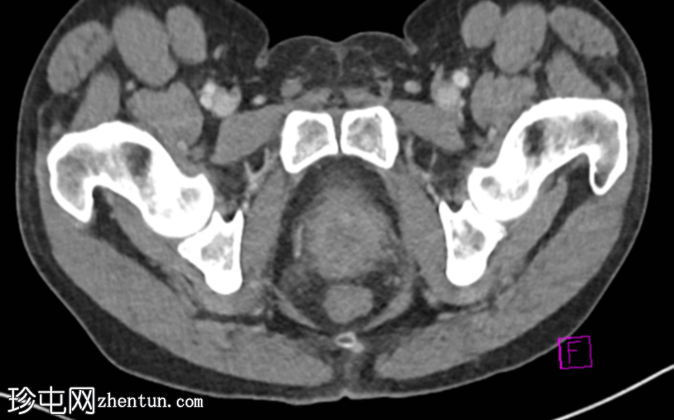

前列腺增大,前列腺内可见分隔性低密度病灶

前列腺周围轻度炎症性脂肪浸润,伴脓肿

与其他病因相比,类鼻疽引起的前列腺脓肿通常为双侧性、多灶性,并具有特征性的多房性外观。

影像

学鉴别诊断包括结核样脓肿、其他细菌性前列腺炎和恶性

肿瘤

。